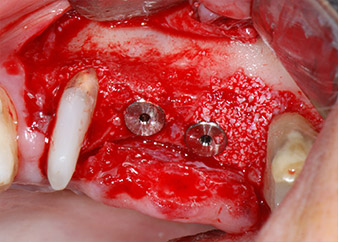

The implants (Restore, Keystone Dental, diameter 3,75 mm, length 8.0 mm) were placed with the implant motor (Figs. 11 and 12).

Bone deficiencies around the implants, at the mesial aspect of tooth 27 and around the buccal root of tooth 24, were filled with xenogeneic bone substitute particles and covered with an absorbable collagen membrane (Bio-Gide, Geistlich Biomaterials) for GBR augmentation (Figs. 13 and 14).